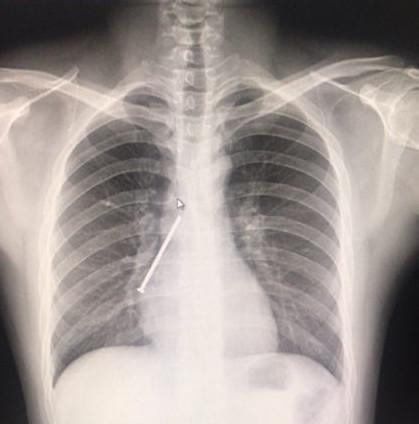

怀孕前做过胸片,要间隔怀孕三个月后再准备怀孕,B超对卵泡发育不成问题,建议,没有怀孕必要做。X射线对胎儿有致畸的作用,长此以往孕妇恶性变化就会大,会因卵细胞死亡导致贫血,胎儿畸形。所以,建议整个孕期不要选择胸透,也不要使用X射线。